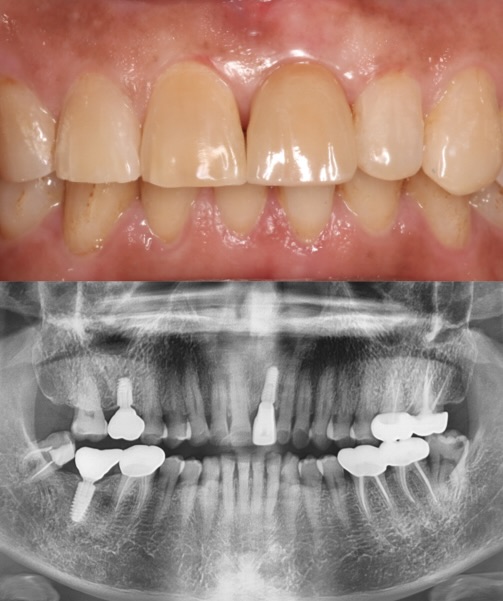

FULL MOUTH REHABILITATION

This case showcases a complete smile transformation for a patient with severe bruxism (teeth grinding). Through expert planning, full zirconia crowns were used to rebuild worn teeth, while dental implants were placed in the lower back for long-term strength and stability. The Work done at Moral Dental Clinic, the result is a durable, natural-looking smile—restored in both form and function.